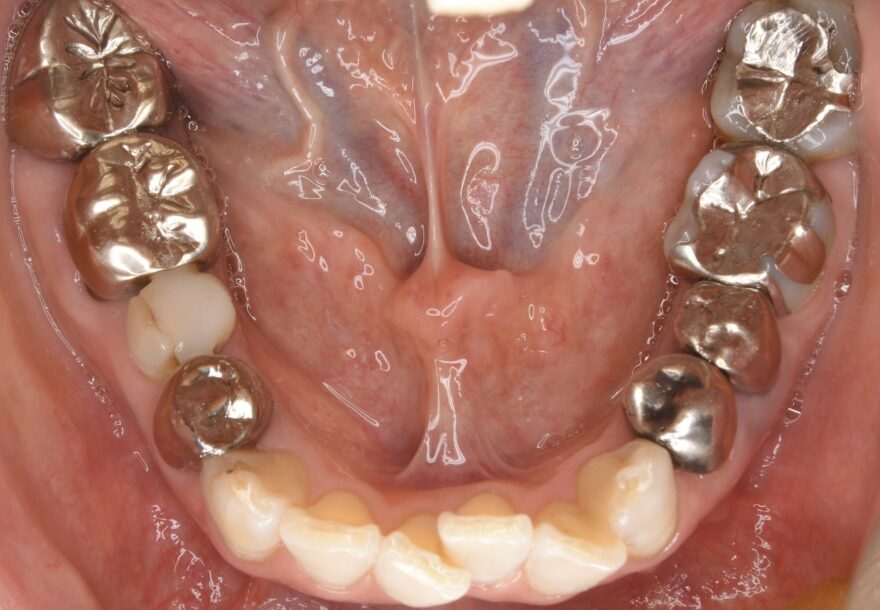

初診時の口腔内写真

銀歯の中が虫歯になっていることがわかります。

こちら側の銀歯も適合の問題を抱えていることがわかります。